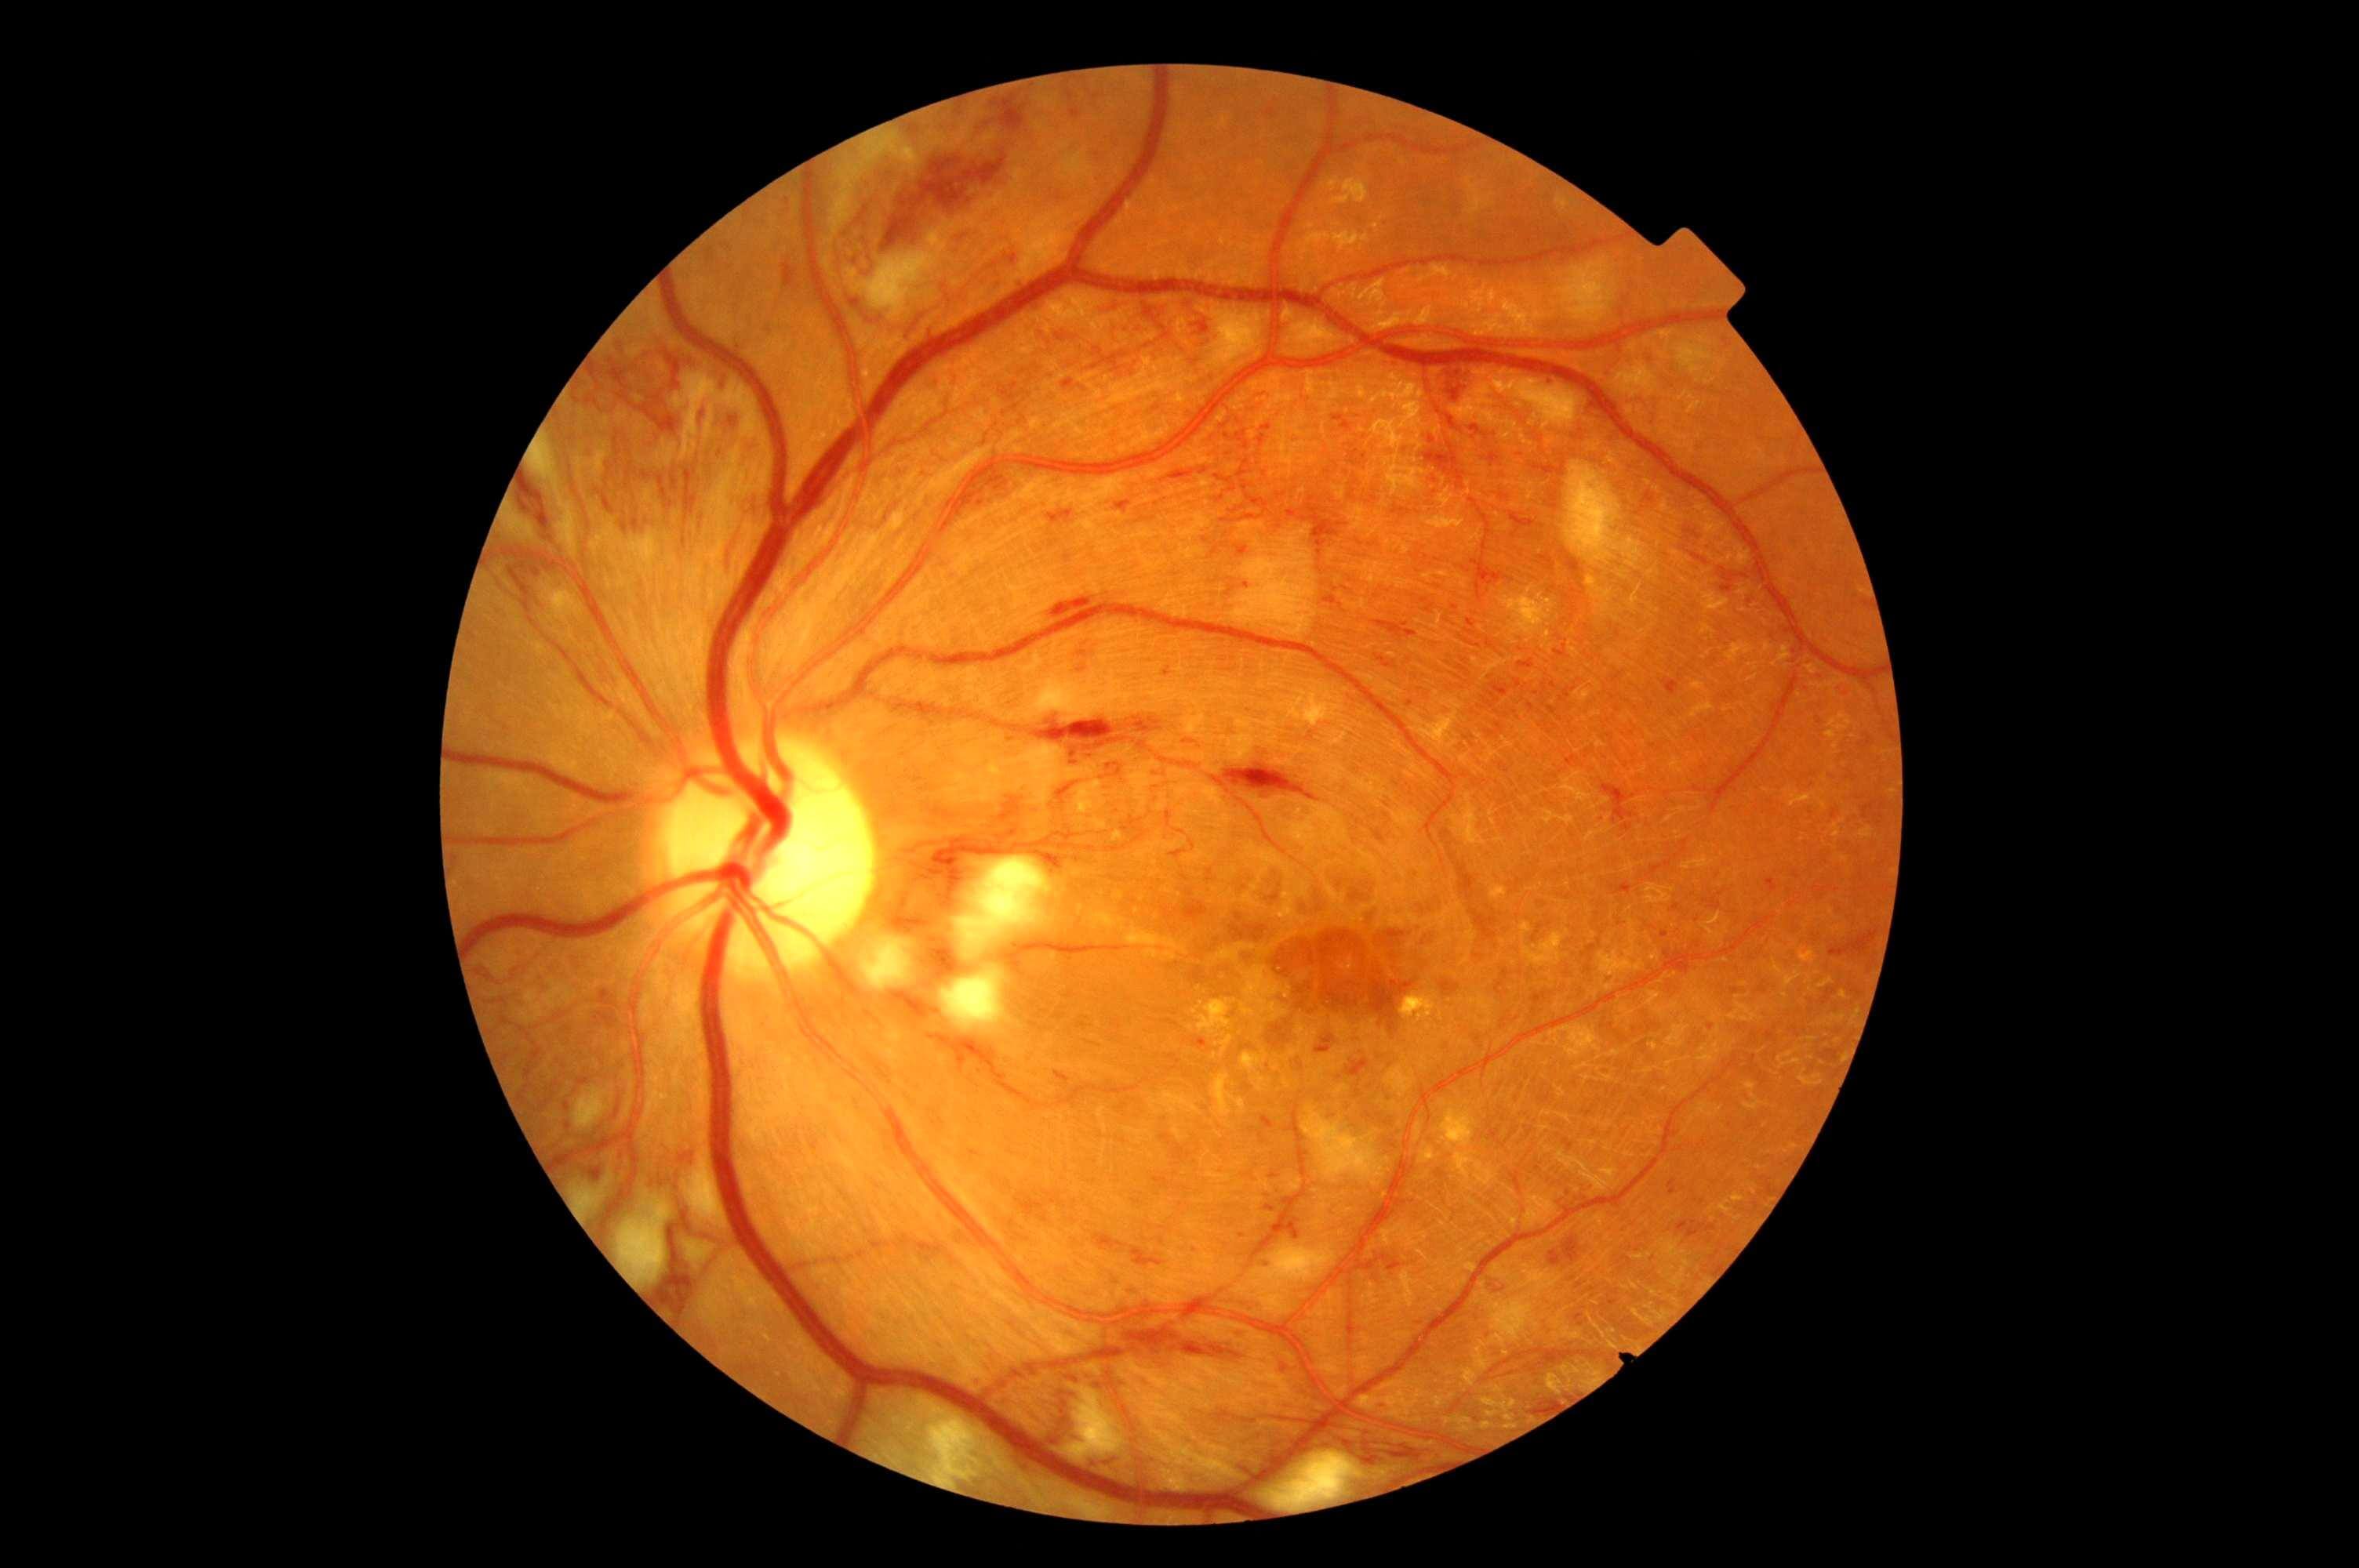

Previously only found in eye hospitals, this new piece of technology will allow us to more easily and accurately detect eye conditions such as age related macular degeneration (AMD), glaucoma and diabetic retinopathy.

The OCT also captures a digital photograph of the surface of the eye at the same time, and this can then be cross-referenced with any areas of concern.

The scan shows us beneath the surface of your retina, so we can see and better understand the very fine changes which can be indications of something unhealthy or abnormal.